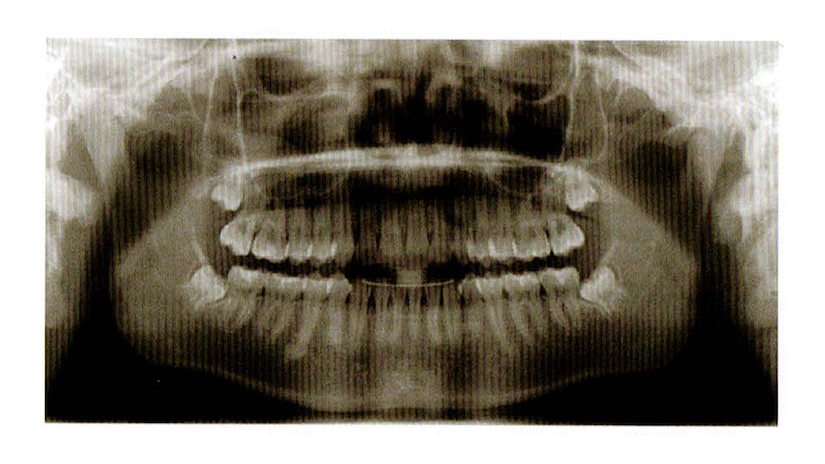

パノラマ撮影(お口のレントゲン)

🩺 特徴

・お口全体を一度に撮影できるレントゲン

・虫歯や歯周病、親知らずの状態を確認できる

・撮影時間はわずか数秒

😊 患者さんにとってのメリット

✔ 被ばく量が少なく、安全性が高い

✔ 口の中にフィルムを入れる必要がないので楽に撮影できる

✔ 歯並びやかみ合わせ、顎の骨の状態を一目で確認できる 💡 こんなときに役立ちます!

・虫歯や歯周病のチェック

・親知らずの診断

・顎の骨の状態や歯並びの確認